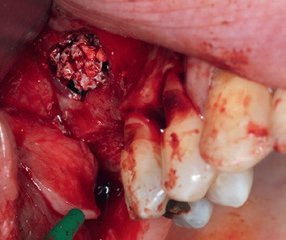

In Lokalanästhesie wurde mit einer vertikalen Entlastung an Zahn 24 und einer marginalen Schnittführung 25, welche mittig im Bereich der Linea alba nach distal fortgeführt wurde, ein Mukoperiostlappen gebildet. Der dreidimensionale Defekt wurde mit einer Präparation nach palatinal dargestellt und das Titangitter auf seine Passform kontrolliert. Bereits zum jetzigen Zeitpunkt erfolgte eine Periostschlitzung für einen späteren spannungsfreien Wundverschluss. Nach Ausdünnung des Knochenfensters mit dem Safescraper wurde das bukkale Fenster für den externen Sinuslift präpariert und die Schneider-Membran angehoben. Diese zeigte sich als vollständig intakt. Aufgrund des großen Augmentationsvolumens wurde zusätzlich retromolar in regio 47/48 mit einem Trepanbohrer autologer Knochen entnommen (Abb. 2) und mit einer Knochenmühle in kleine Knochenspäne zerkleinert. Das Mischverhältnis im Bereich der Augmentation lag bei einem Anteil von 50% autologem Knochen mit 50% bovinem Knochenersatzmaterial (Bio-Oss, Geistlich) (Abb. 3), wobei im Bereich der Kieferhöhle mit etwas mehr DBBM und nur einer geringeren Menge an autologen Knochenchips gearbeitet wurde. Nach dem Auffüllen des Sinus (Abb. 4) wurde das individuelle Titangitter mit leicht rüttelnden Bewegungen auf den Defekt gesetzt und dessen Passform an den Füßchen am Rande des Gitters überprüft. Anschließend wurde es mit 2 Osteosyntheseschrauben lagestabil fixiert (ADS Schrauben, American Dental) (Abb. 5) und zusätzlich mit einer Kollagenmembran abgedeckt (Biogide, Geistlich) (Abb. 6). Es erfolgte ein primärer Wundverschluss mit 2 tiefen Matratzennähten und einer fortlaufenden Naht (Seralon 5/0, Serag-Wiessner) (Abb. 7). Postoperativ wurde die Patientin gebeten, für 2 Wochen das Schnäuzen der Nase zu unterlassen.